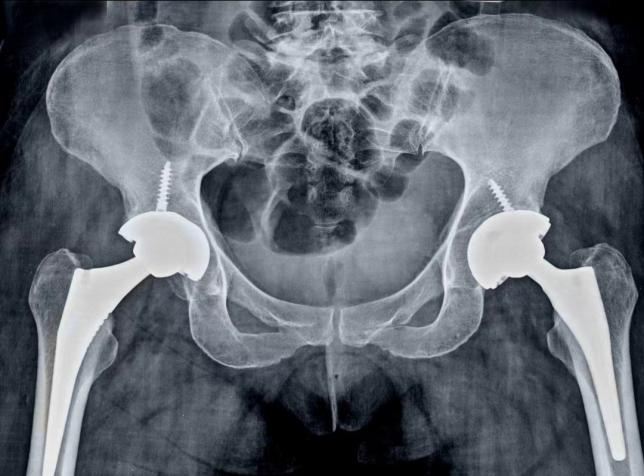

同时,骨科一病区行政主任易平邀请中南大学湘雅二医院骨科李辉教授主刀,易平主任团队配合完成手术。手术团队凭借精湛的技术和丰富的经验,仅用时两小时,并将出血量控制在200毫升到250毫升,成功避免了并发症和意外情况的发生。术后,医护团队立即指导患者进行踝泵运动和双下肢气压理疗,促进血液循环,预防血栓。

术后第二天,刘大姐在助行器的辅助下下地行走。在医护团队的精心照料下,患者顺利出院。一个月后,刘大姐自行步行来门诊复查,恢复情况良好。至此,刘大姐的双髋重生之旅圆满结束,涅槃重生步入正常生活。